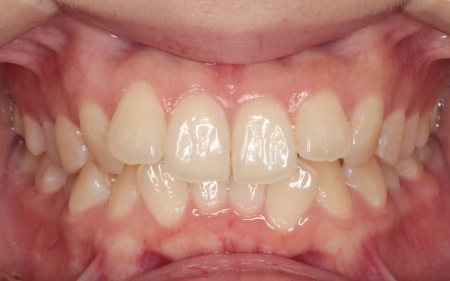

治療後

| 行った治療内容 | 患者様は「できるだけ目立たない治療方法で、なるべく早く終わらせたい」と希望されていたため、ハイブリッド矯正を提案し、同意いただきました。 ハイブリッド矯正とは、ワイヤー矯正とマウスピース矯正の両方を行う方法です。先にワイヤー矯正で歯を大きく移動させたあと、マウスピース矯正で仕上げることで、治療期間の短縮が望めます。 ただ2種類の矯正装置を使用するため、単独での矯正治療よりも費用が高くなる点がデメリットです。 ・ワイヤー矯正 歯の表面にブラケットと呼ばれるボタン状の装置を接着し、そこにワイヤーを通して歯を移動させる方法です。 患者様は目立たない治療方法を望まれていたため、ブラケットには白く目立ちにくい「セラミックブラケット」を選択しました。 ・マウスピース矯正 患者様専用のマウスピース(アライナー)を複数個作製して、定期的にご自身で交換しながら歯を移動させる方法です。 今回は、アライナーの枚数に制限がないプランである「インビザライン・コンプリヘンシブ」を選択しました。 まずは歯の表面にセラミックブラケットを装着し、ワイヤー矯正で歯を全体的に移動させます。 歯並びがある程度正しい位置に並んだら、マウスピース矯正で微調整を行いました。 歯の移動が完了したあとは定期的に経過を確認しながら、後戻りを防ぐためのリテーナー(保定装置)を継続して使用いただき、治療を終了しました。 |